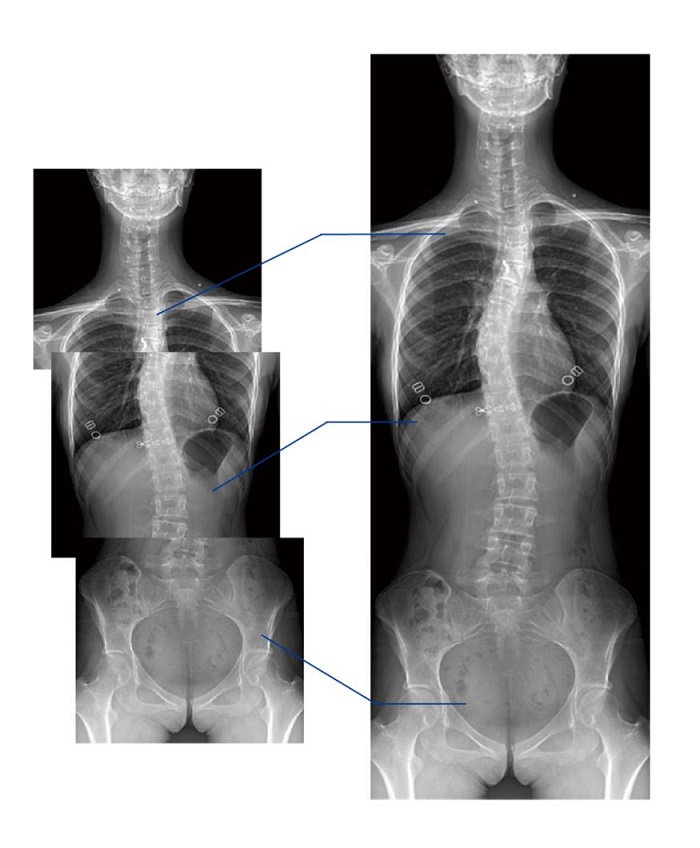

全景拼接功能

全景拼接功能是在全景影像拍攝的情況下,拍攝各個部位的影像,得到的圖像最終合成一幅全景圖像。適用于輔助脊柱畸形矯形治療、康復(fù)檢查,可對脊柱、下肢及下肢靜脈造影進行分段攝片,然后對分段圖像進行拼接,在一幅X光圖像上完整顯示全脊柱或下肢整體形態(tài),為臨床提供高精度圖像。